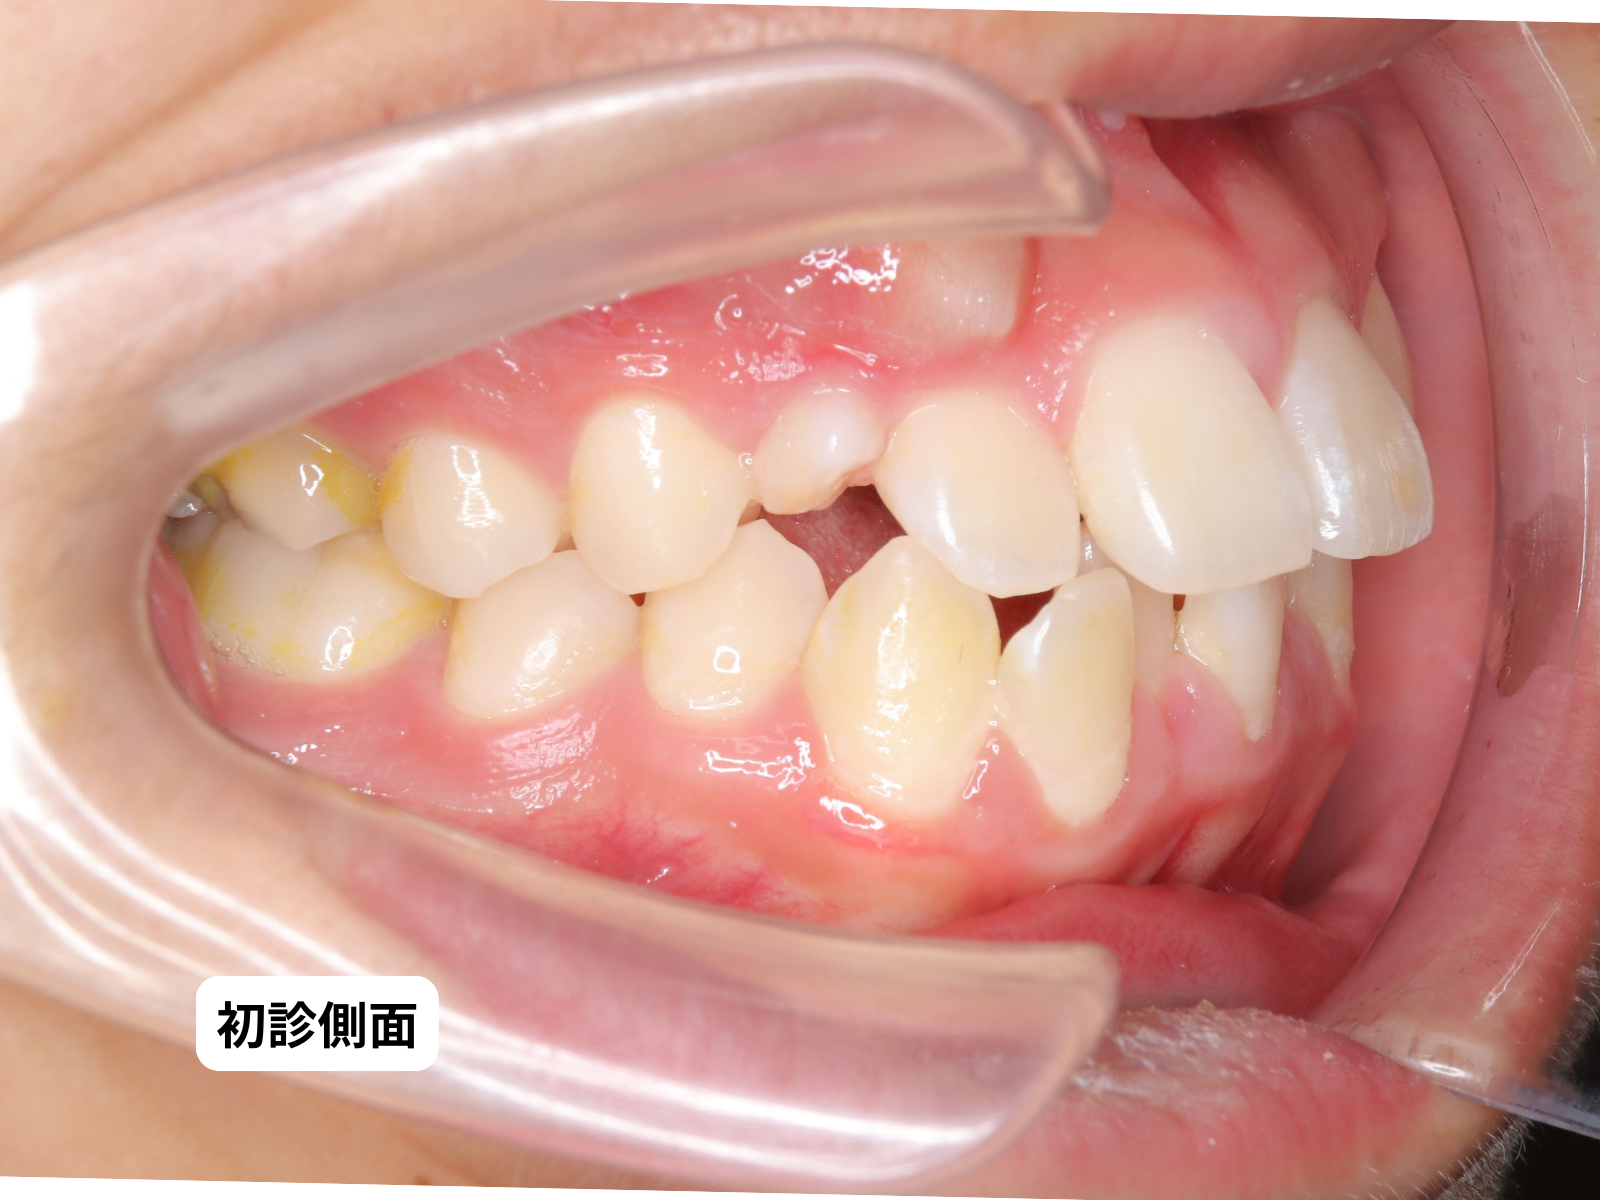

犬歯埋伏 初診時の口の中|奈良の矯正歯科 氏井矯正歯科クリニック

口の中:右上C(乳犬歯)がまだ残っている

初診時(治療前)

一見すると「よくあるガタガタ」。ところが上顎右側には、乳犬歯が残ったまま永久犬歯が見当たらない。前歯は重なり合い、口元は前に突出している状態。